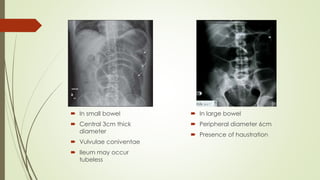

 In small bowel

 Central 3cm thick

diameter

 Vulvulae coniventae

 Ileum may occur

tubeless

 In large bowel

 Peripheral diameter 6cm

 Presence of haustration

Fluid levels with gas above;

‘stepladder pattern’. Ileal

obstruction by adhesions;

patient erect.

Supine radiograph from a patient with

complete small bowel obstruction

shows distended small bowel loops in

the central abdomen with prominent

valvulae conniventes (small white

arrow)

Figure 3. Lateral decubitus

view of the abdomen, showing

air-fluid levels consistent with

intestinal obstruction (arrows).